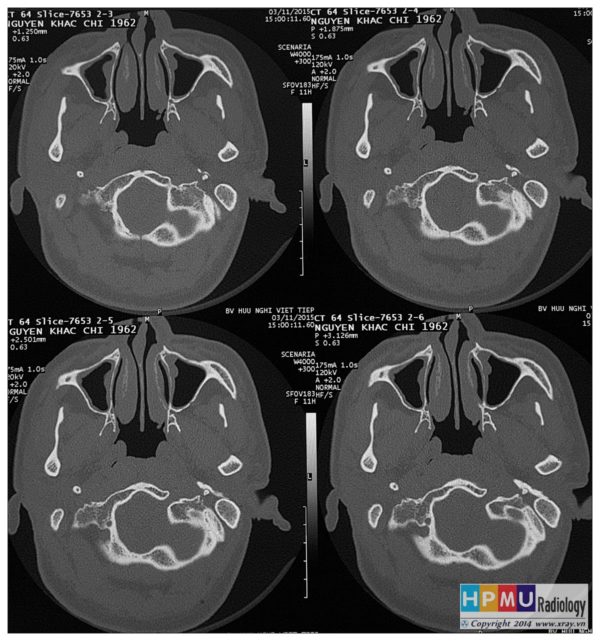

Ca lâm sàng » Tai Mũi Họng » Viêm xoang

Viêm xoang

» Thông tin: Nam giới – 56 tuổi.

» Lâm sàng: Đau đầu.

Danh mục: Tai Mũi Họng